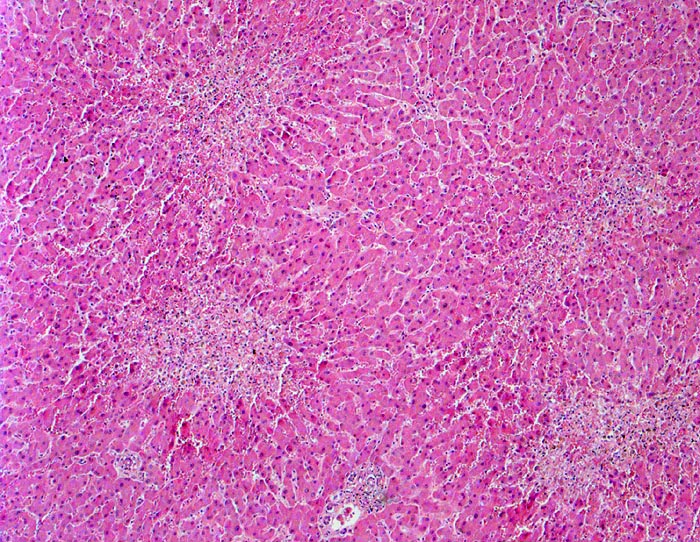

Linksherzversagen oder ein Schockzustand können zu einer hepatischen Minderperfusion mit ischämischen Koagulationsnekrosen der perivenulären Hepatozyten führen. Die Kombination von Hypoperfusion und retrograder Stauung (Rechtsherzversagen) führt zu zentrilobulären hämorrhagischen Nekrosen. Klinisch führen diese Nekrosen zu einer transienten geringen bis mässigen Erhöhung der Transaminasewerte, gelegentlich auch zu einem leichten Ikterus.

Metastasierendes Kolonkarzinom. Als Todesursache fanden sich nicht ganz frische zentrale und perizentrale Lungenembolien.